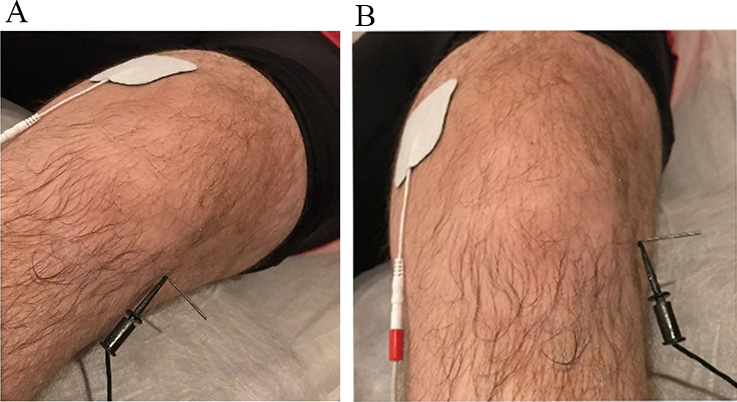

Fig. 3.

Fig. 3.Placement of the electrodes for the application of electrolysis on the patient’s knee. (A) Sagittal. (B) Frontal. We can see a real image of the treatment with electrolysis and how the positive electrode (anode) is located about 10 cm from the negative electrode (cathode). The positive electrode is connected to a self-adhesive patch. The negative electrode is connected to a sterile surgical steel needle 40 mm long, positioned at the deep interface of the patellar tendon.